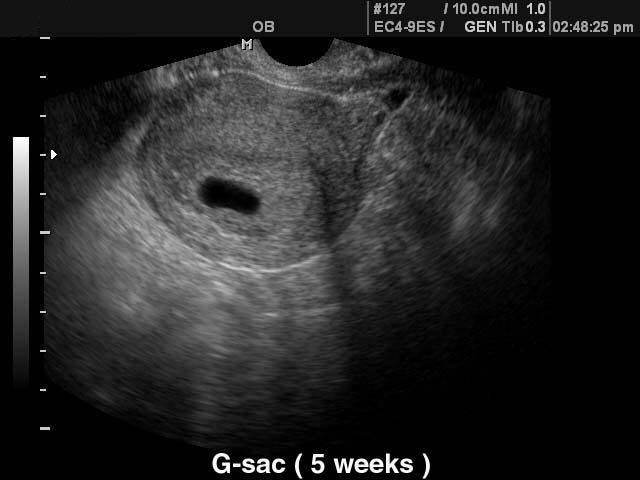

Нет ничего. Плодное яйцо выглядит вот так Изображение Черное пятнышко.